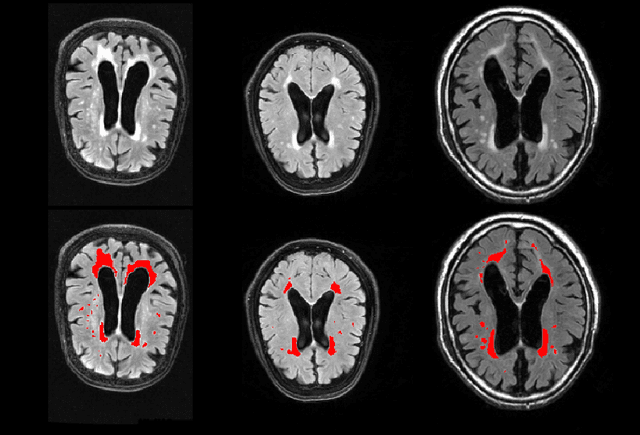

Abstract:Segmentation has been a major task in neuroimaging. A large number of automated methods have been developed for segmenting healthy and diseased brain tissues. In recent years, deep learning techniques have attracted a lot of attention as a result of their high accuracy in different segmentation problems. We present a new deep learning based segmentation method, DeepMRSeg, that can be applied in a generic way to a variety of segmentation tasks. The proposed architecture combines recent advances in the field of biomedical image segmentation and computer vision. We use a modified UNet architecture that takes advantage of multiple convolution filter sizes to achieve multi-scale feature extraction adaptive to the desired segmentation task. Importantly, our method operates on minimally processed raw MRI scan. We validated our method on a wide range of segmentation tasks, including white matter lesion segmentation, segmentation of deep brain structures and hippocampus segmentation. We provide code and pre-trained models to allow researchers apply our method on their own datasets.